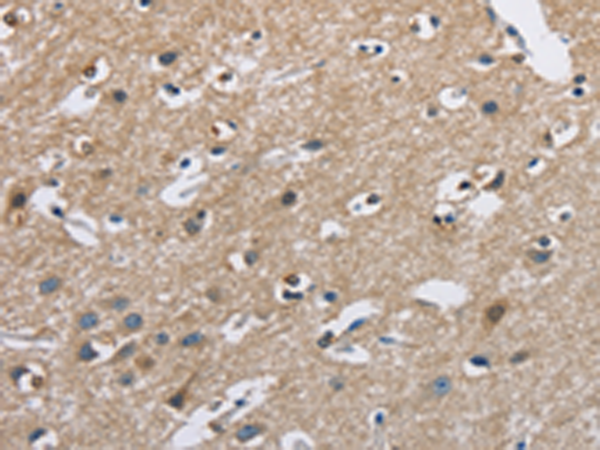

分类: 科研抗体货号: P01143别名: MO2L; MO25-BETA; bA103J18.3; RP11-103J18.3应用: WB,IHC反应种属: Human, Mouse